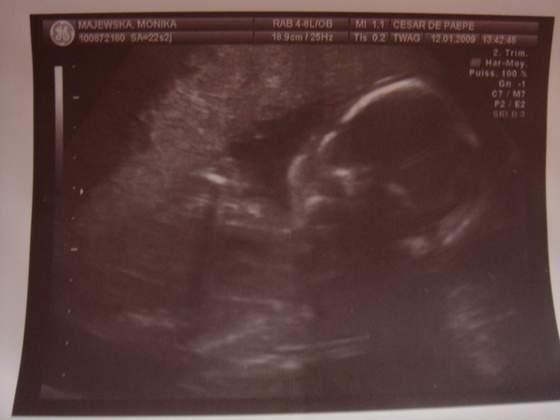

jutro ide na usg do szpitala i badania to sie zapewne juz dowiem.

a 20tego w moje urodzinki do ginki lece i jeszcze raz obejrze maluszka

Odezwe sie jutro jak wroce z usg